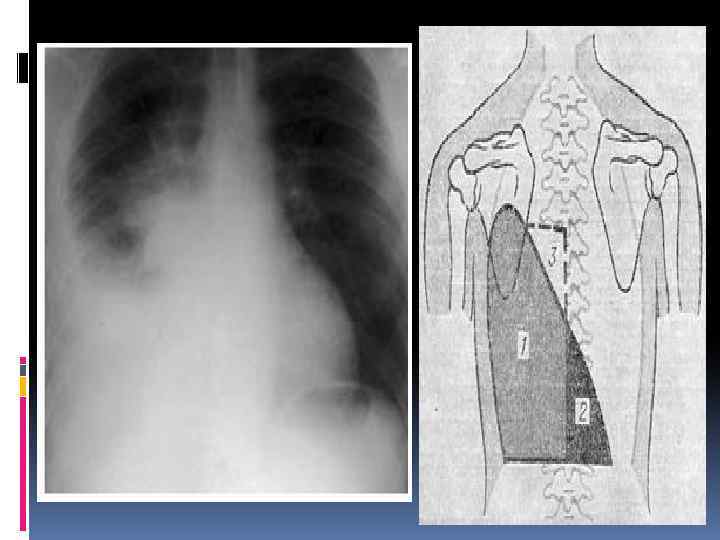

Рентгенологическое исследование Рентгенологические признаки сухого плеврита: высокое стояние купола диафрагмы, отставание его при глубоком вдохе, ограничение подвижности нижних лёгочных границ, лёгкое помутнение части лёгочного поля, тупой срезанный рёбернодиафрагмальный угол и затенение задней части диафрагмы в боковой проекции. В наружных отделах жидкости больше, поскольку лёгкое поджато к корню, что приводит к появлению косой, а не горизонтальной границы тени. ЭКГ имеет дифференциально-диагностическое значение при левосторонний плевритах для исключения инфаркта миокарда. Следует помнить, что большие выпотные плевриты и грубые спайки способны смещать средостение и менять расположение электрической оси сердца.